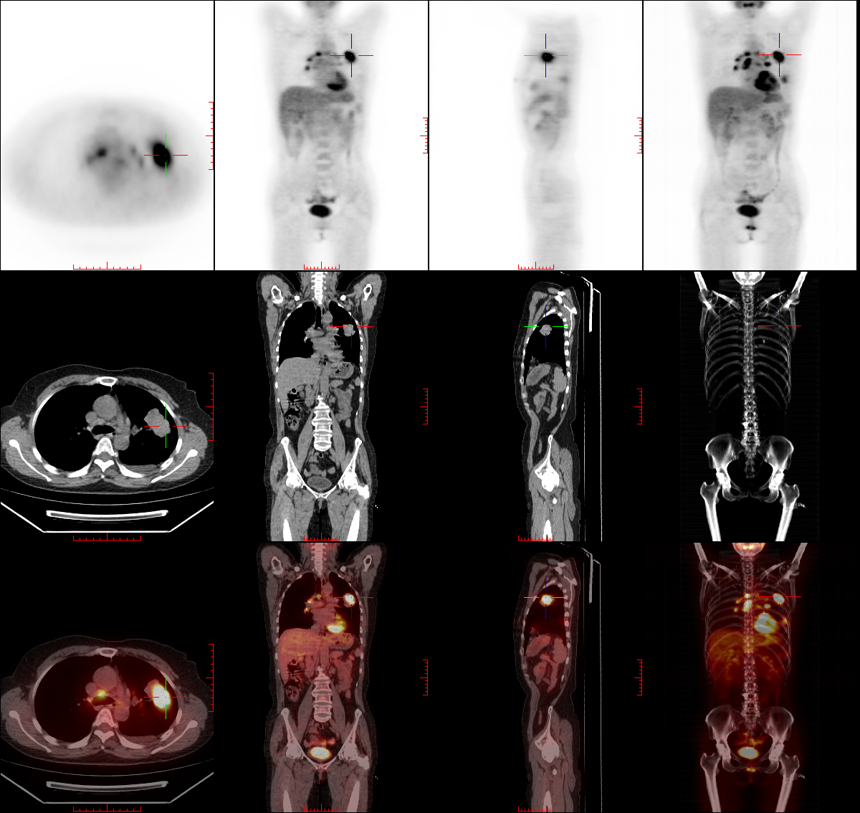

+ Z8 {' _0 n0 E7 g" ]+ M7 `10-17复查PET-CT 再分期:左肺下叶鳞癌 cT4N3M1a,双肺门、纵隔淋巴结转移,肺内转移,胸膜转移,PD-L1 0,EGFR L858R+,EGFR扩增。 治疗: 2025-10-23 开始口服阿法替尼 2025-11-24复查结果提示病变较前略有缩小,疗效评价SD,医生建议继续口服阿法替尼治疗。 & }6 X( a' x8 g2 D$ h

吕岩教授(影像科) 从影像学角度分析,患者原发病灶缩小明显,疗效显著。初诊时肺内存在多发磨玻璃结节及少量小实性结节,随访中磨玻璃结节无明显变化,考虑转移可能性较低;实性结节因初始体积过小,CT对其敏感性有限,PET-CT检测出代谢活性,为诊断提供了关键补充。

/ k7 ]4 _' o4 d临床中此类情况较常见,原发灶为实性者,转移灶多以实性为主。CT仅能观察病灶形态、大小,小病灶增强扫描强化不明显时,难以判定是否为转移;PET-CT可通过代谢活性辅助判断,是CT诊断的重要补充手段。整体来看,结节的动态变化特点与李红霞教授观点一致,需持续动态观察评估。 5 @/ W. ^% ]5 u2 ~4 y) k

李红霞教授(肿瘤内科) 10月17日复查的PET-CT报告准确简洁,已明确判定纵隔淋巴结及双肺转移,据此可确定患者为Ⅳ期病变,因此当时以全身治疗为主,予阿法替尼口服。对比10月PET-CT与11月CT影像,病灶整体略有缩小,疗效评估为疾病稳定(SD),提示当前全身治疗方案有效。